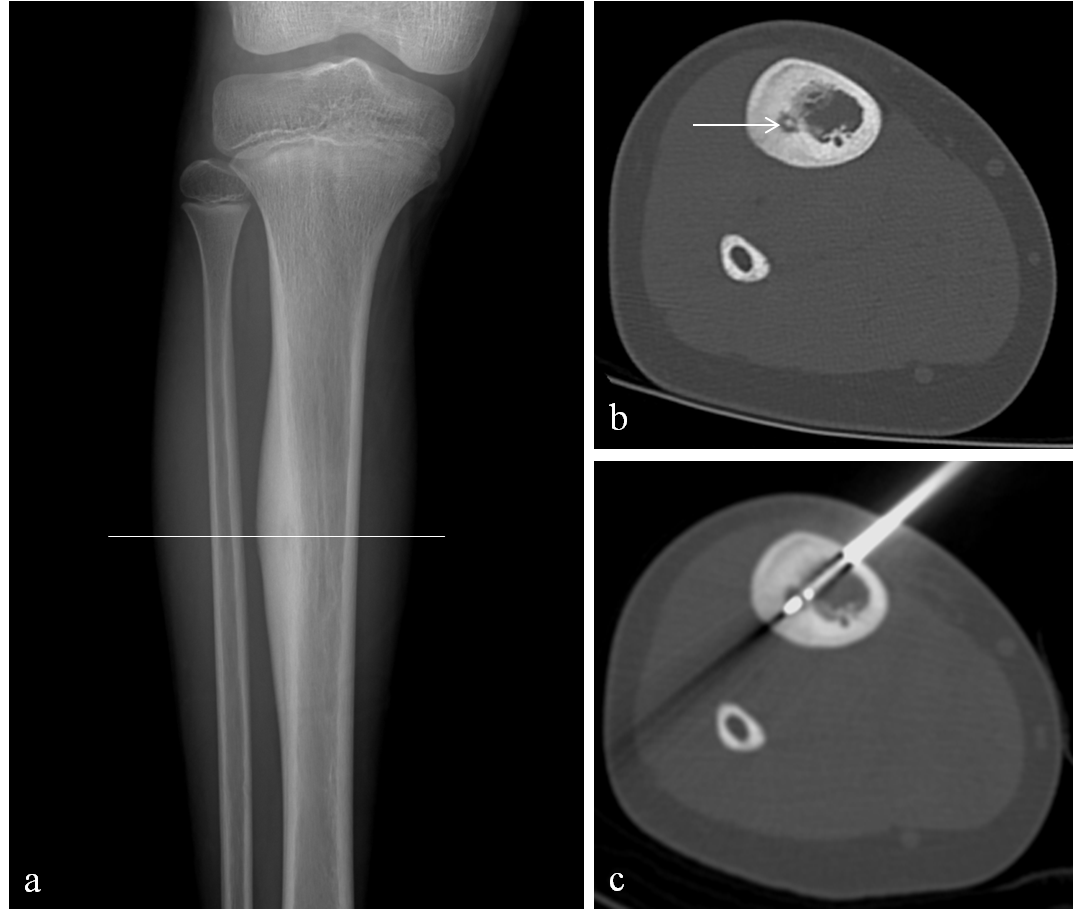

Osteoid osteoma is a benign lesion of bone, typically involving children and young adults between 5-25 years old. Despite its benign histologic nature, patients with osteoid osteoma often present with significant dull aching pain and discomfort which may worsen and become severe, especially in the evening. Unfortunately, many patients suffer with this pain for years before either seeking medical care or receiving the correct diagnosis. After clinical assessment, diagnosis is often made on radiographs as a focal area of reactive cortical thickening and sclerosis with a small central lucent nidus (Fig 1a). Occasionally, CT is required to confirm the diagnosis and can be helpful for pre-interventional planning (Fig 1b).

3). Next, the appropriate radiofrequency probe will be advanced into the lesion which is heated at 85 to 90 degrees Celsius for 6 minutes (Fig 1c).

Figure 1: 10-year-old boy with right tibia osteoid osteoma (OO). (a): Right leg radiograph demonstrates reactive cortical sclerosis. (b): Axial CT image obtained through the right tibia at the level of the cortical sclerosis (white line in a) demonstrates the OO nidus (arrow) prior to advancing the RFA electrode across the OO (c).